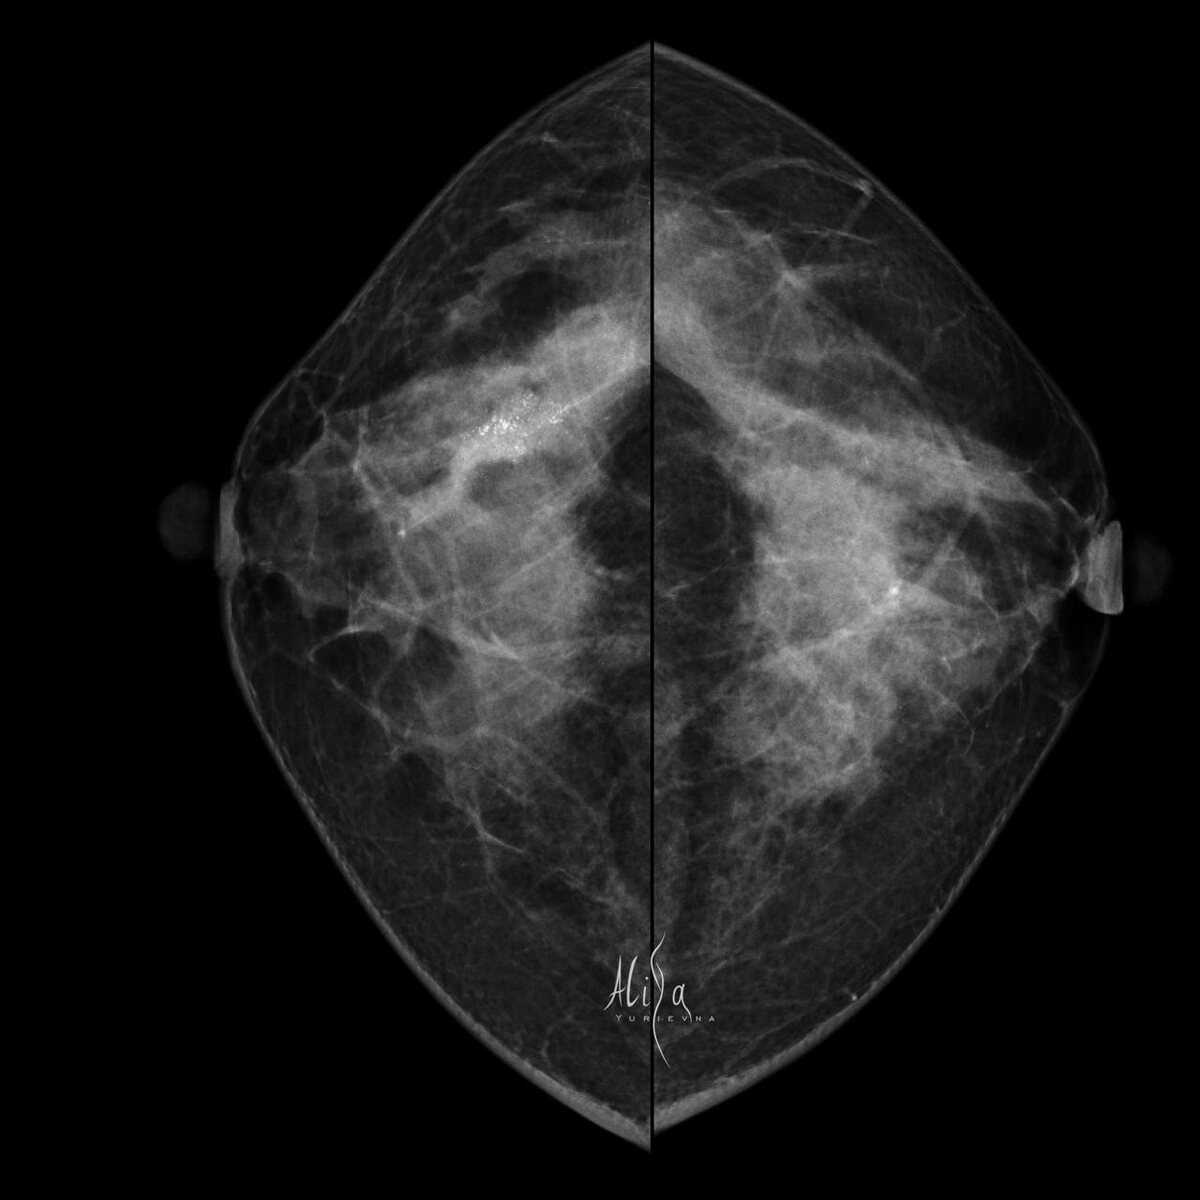

Женщина 41 год  Жалоб нет. Первая маммография.  История практически ежедневная. Что поможет не пропустить патологию? Правильное, последовательное выполнение методик.  Сначала — маммография, потом УЗИ.  Такие кальцинаты достаточно хорошо видны при УЗИ, если ваш мозг знает, ЧТО искать и КАК они будут выглядеть.  И биопсию, кстати, вы здесь тоже легко выполните под узи контролем.  Гистология: cTis (dcic)cN0cM0 Морфологическая картина представлена карциномой in situ high grade.

Женщина 41 год

Жалоб нет. Первая маммография.

cTis (dcic)cN0cM0 Морфологическая картина представлена карциномой in situ high grade.